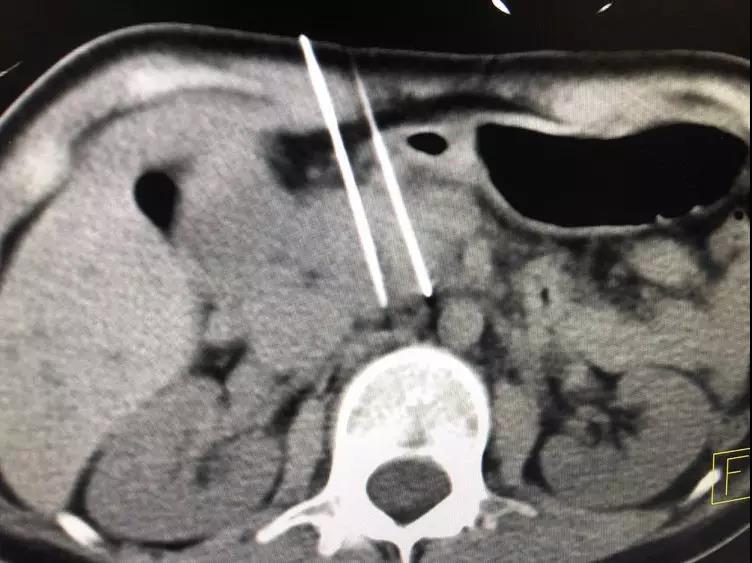

纳米刀消融胰腺肿瘤中

消融三个器官的肿瘤是由于莉莉的情况紧急,肿瘤处于快速生发期,考虑到器官多但是每个器官的肿瘤都不大,莉莉年轻身体好,经与多个专家的讨论,要控制肿瘤必须多管齐下,决定实行同步化疗加纳米刀一次性三个部位的同期消融手术。

一般情况是不主张一次性消融三个器官的肿瘤,由于莉莉的情况特殊,肿瘤处于快速生长期,考虑到器官多但是每个器官的肿瘤都不大,莉莉年轻身体好,经与多个专家的讨论后,要控制肿瘤必须多管齐下,决定由牛博士实行同步化疗加纳米刀一次性三个部位的同期消融手术。

术后牛博士也表示能够完成这次有挑战性的手术表示很欣慰:“在充分评估安全的情况之下,我们今天一次消融三个器官的肿瘤,,最重要的是抢了时间控制爆发期的肿瘤,为下一步的治疗提供了时间和基础!截止今日,今年我已经完成142台纳米刀手术,超过了去年全年141台的手术量,纳米刀,目前已经成为我院的的常规手术。”